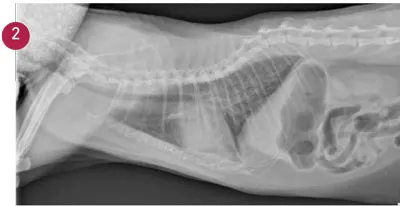

Plasma NT-proBNP concentrations are elevated in dogs and cats with congestive heart failure and those with asymptomatic heart disease (Figure 2). Several studies have shown plasma BNP or NT-proBNP to be sensitive and specific for the diagnosis of heart failure in dogs and cats presenting with cough or dyspnea (Table 1).9–13

FIGURE 2

Lateral thoracic radio­graph from a 10-year-old castrated male domestic shorthair cat with vague clinical signs of lethargy and loss of appetite of 1 day’s duration. No murmur or gallop was noted. The only physical examination abnormality was an elevated respiratory rate (60 breaths/min). Thoracic radiographs were suspicious for congestive heart failure, but the NT-proBNP level (1126 pmol/L) added confidence to the diagnosis.